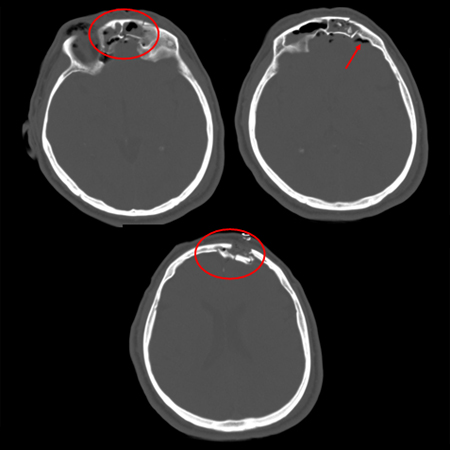

Skull fractures

Fracture of temporal bone

Comminuted depressed skull fracture with pneumocephalus